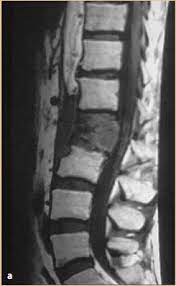

- La espondilitis anquilosante (EA) es una artropatía que se encuentra dentro del grupo de artropatías seronegativas (con antígeno reumatoideo negativo), siendo la entidad más común y representativa de ellas. Se caracteriza por inflamación crónica del esqueleto axial, con dolor de espalda de tipo inflamatorio y rigidez progresiva, que también puede involucrar caderas, hombros, articulaciones periféricas y entesis (que corresponden a sitios de inserción de ligamentos, músculos, fascias o cápsulas en un segmento óseo). Típicamente se manifiesta en pacientes jóvenes que inician su sintomatología entre los 20 y 30 años, que presentan en general buena respuesta a antiinflamatorios no esteroideos. En cuanto a la predilección por sexos, habitualmente se encuentra una relación H:M de 2:1 La enfermedad está fuertemente ligada al antígeno leucocitario humano B-27 (HLA B-27)